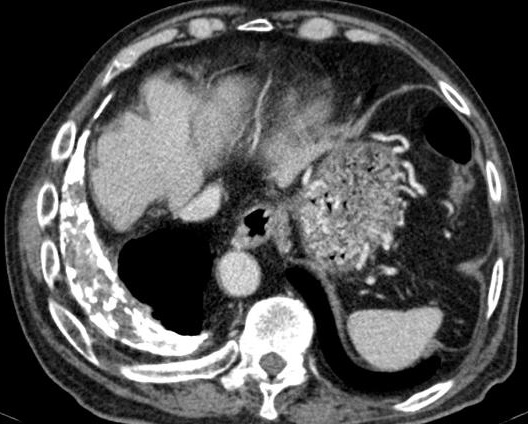

Aspect radiologique du

epaissisement pleurale d'une pleurite tuberculose au

stade restrictive de la plevre . La plevre est epais

, heterogene , hyperdense situe à la region

posterieure , inferieure du poumon droit |